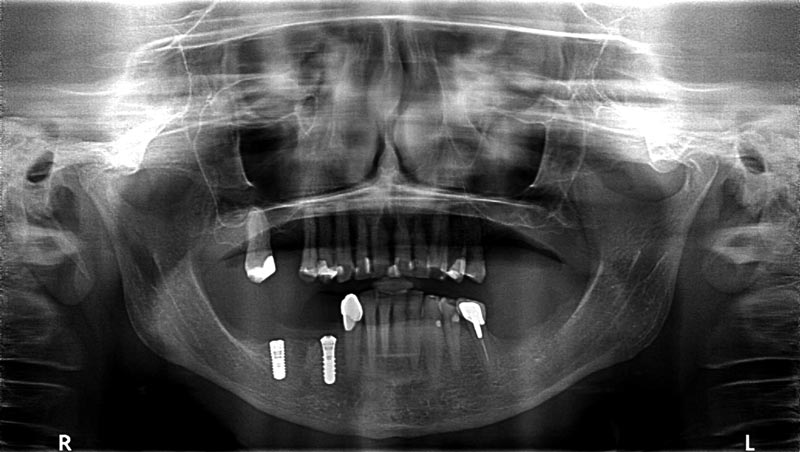

10/14 - Radiological situation post implantation

Block augmentation with maxgraft® in the mandible - PD Dr. Dr. F. Kloss